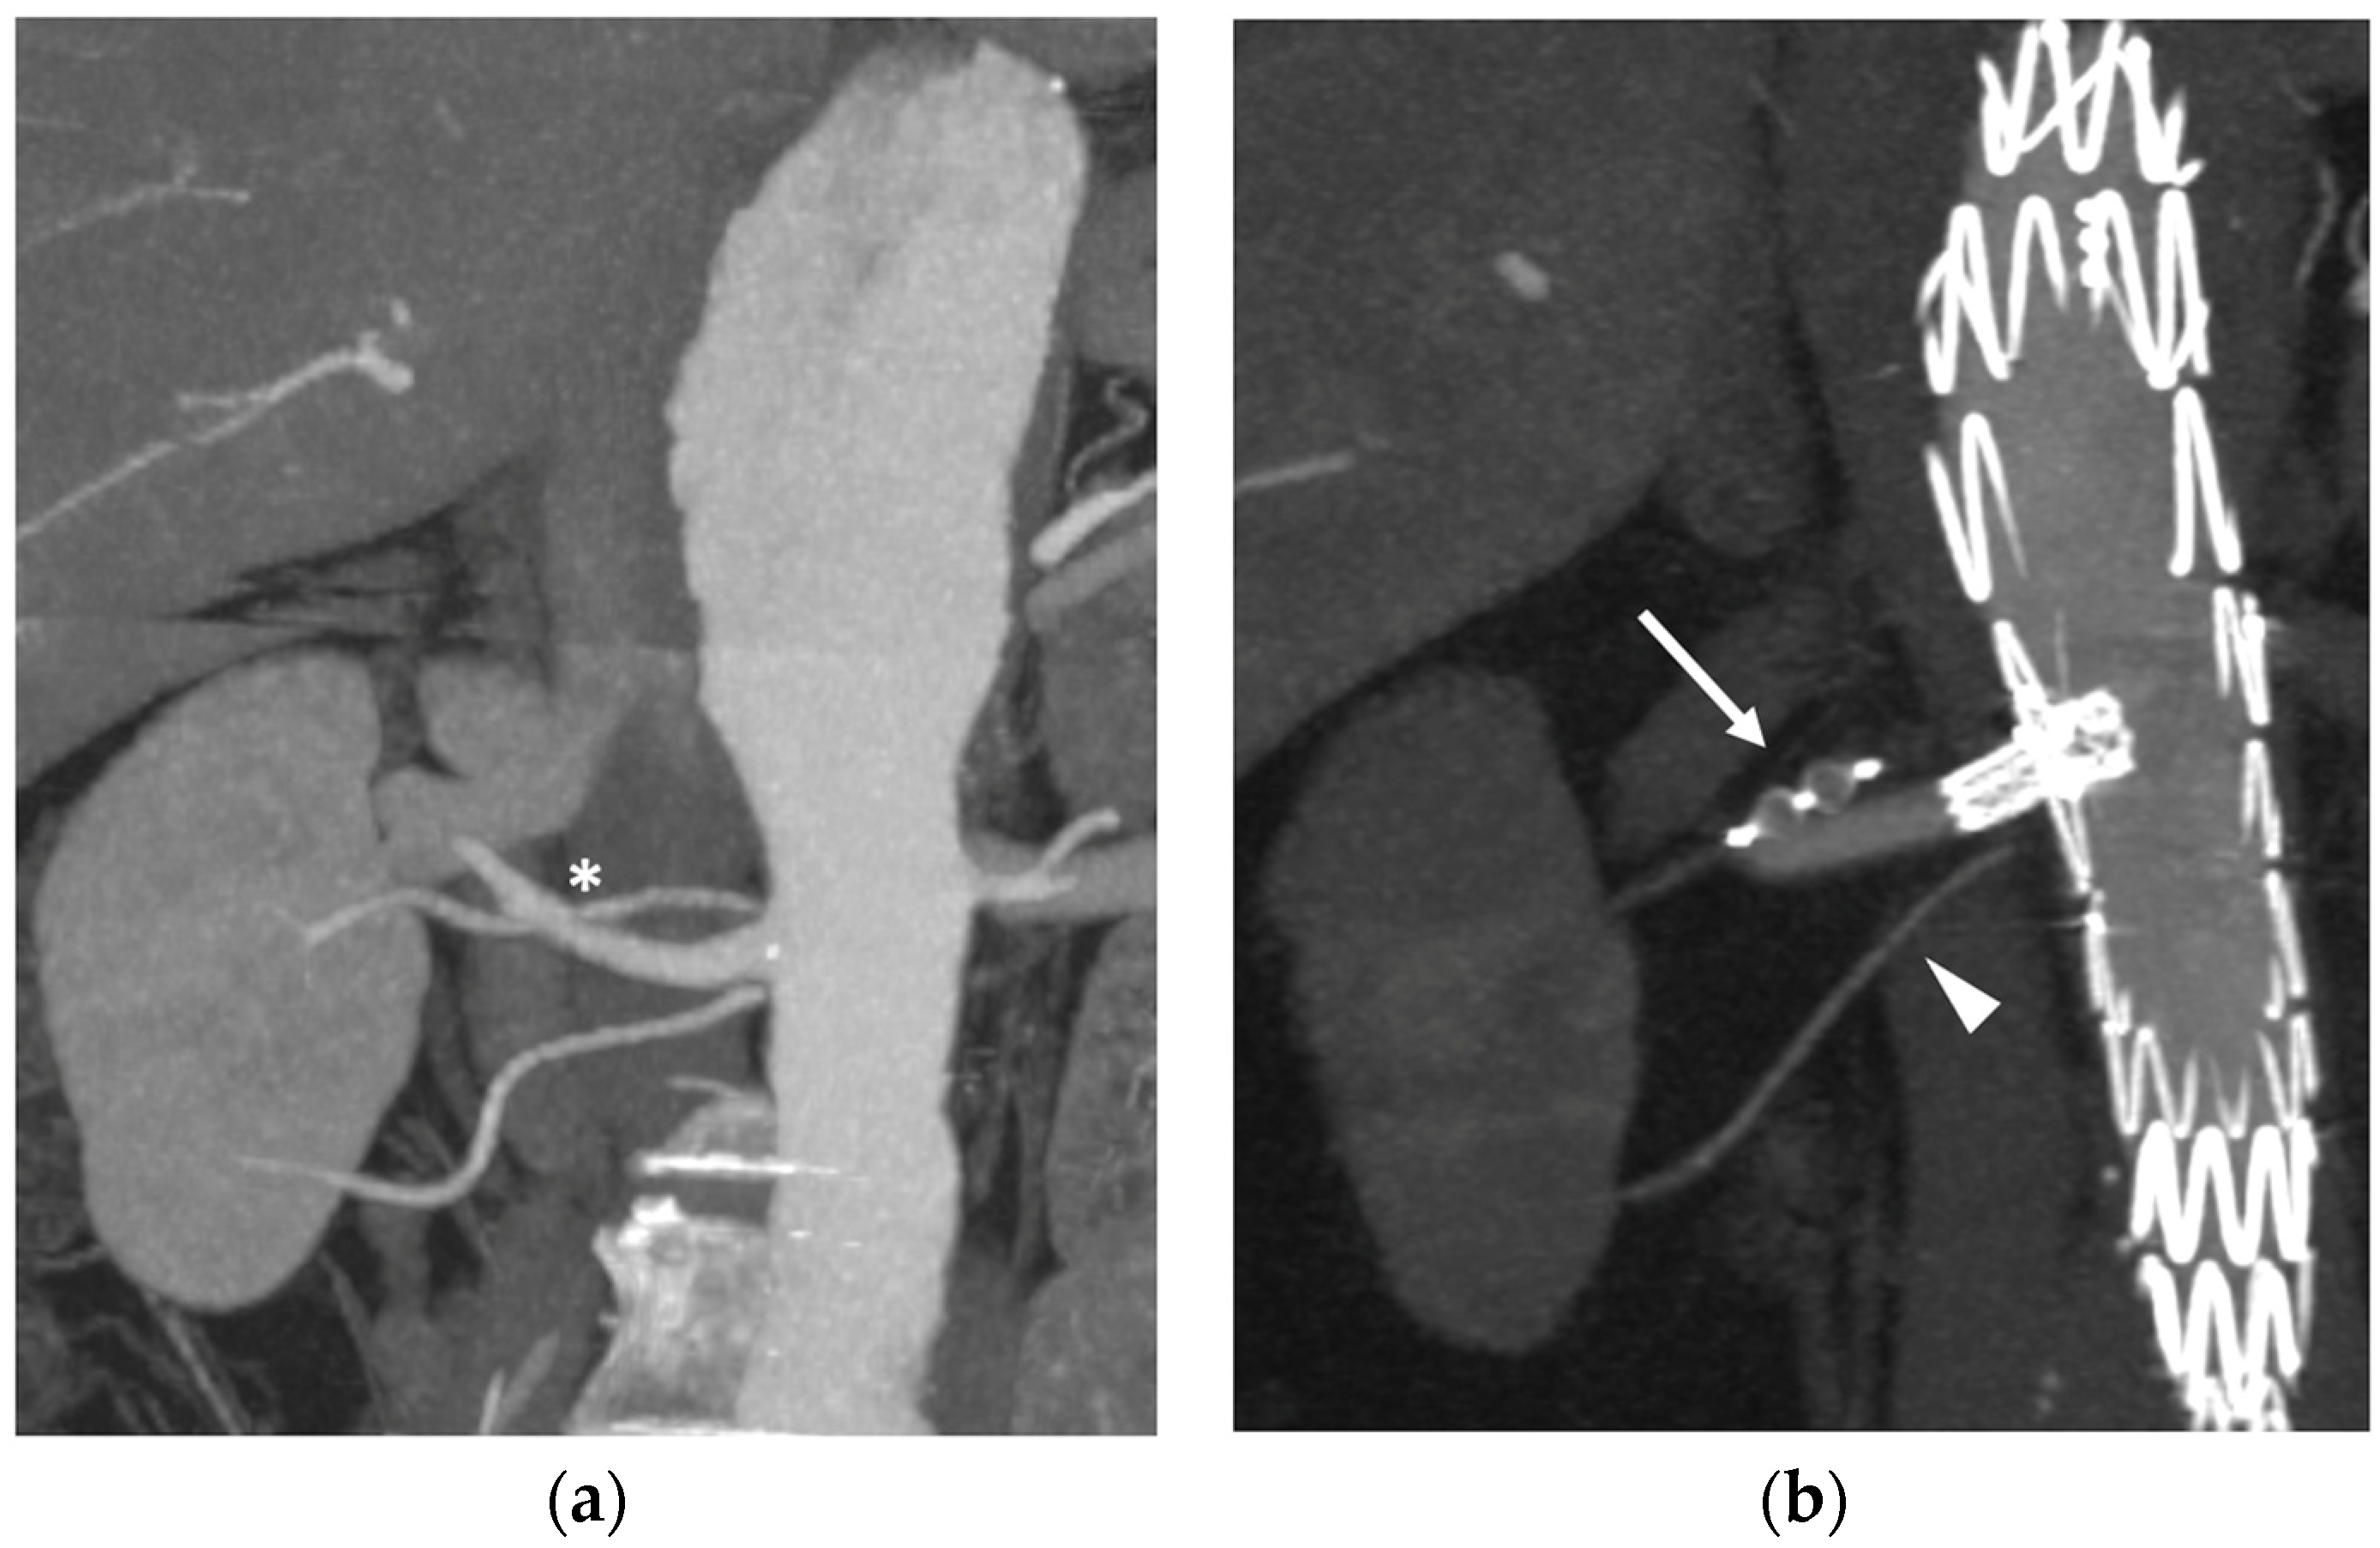

- As a modification of the original technique from Ferreira et al. [44], Tenorio et al. [45] suggested that branch elongation with a balloon-expandable stent before plug release should be the preferred choice in order to extend the sealing zone; the directional branch should be extended at least 20 mm beyond the branch cuff, and the plug should be released entirely within the stent, with no lobes protruding on the outside (Figure 6a). This configuration would limit any plug migration caused by short landing length inside the branch cuff.

- Alternatively, the “dog bone” technique [46] consists of deploying a balloon-expandable stent-graft inside the branch, sizing it 2 mm larger than the branch itself. It should be inflated to 8 mm, and the proximal and distal portions of the stent should be flared with a larger balloon (4 mm more than the branch diameter). An AVP II should then be released at the beginning of the narrowed part, thus creating a bottleneck effect.

- The MVP-7Q (MVP, Medtronic, Minneapolis, MN, USA) has also been used to occlude branches, with promising results in terms of early success and avoiding the use of a further bridging stent–graft, thus reducing overall procedural costs and possibly operating time [47] (Figure 6b). Aside from the economic and technical aspects, the MVP PTFE membrane design guarantees immediate vessel occlusion, which is of paramount importance in symptomatic/ruptured aneurysms, as opposed to the AVP II design which needs time to achieve complete branch thrombosis.